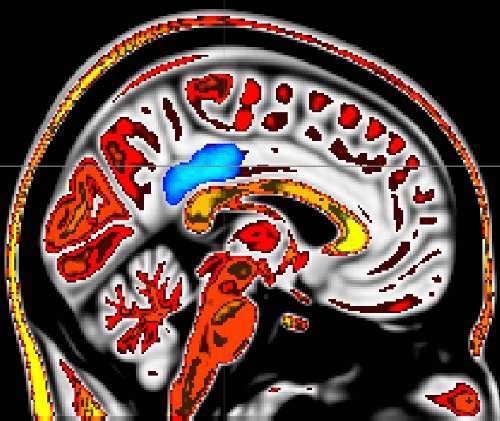

محققان از فناوری MRI برای تصویربرداری از مغز این قبیل افراد استفاده کردند و حین تصویربرداری، افراد را در معرض تحریک حرارتی قرار دادند. تمام تجزیه و تحلیل‌های مغزی نشان داد در افرادی که برای تمرکز بیشتر تفکر می‌کنند، نواحی خاصی از مغز که مربوط به گره عصبی مرکزی شبکه حالت پیش‌فرض مغز است، بیشتر غیرفعال می‌شدند. در افرادی که درد بیشتری حس می‌کنند، فعالیت این ناحیه از مغز بیشتر است.

شبکه حالت پیش‌فرض مغز از قشر ساقه خلفی تا قشر میانی جلویی سر کشیده شده است. اطلاعات معمولا در این دو ناحیه از مغز در رفت و آمد است. این شبکه با پردازش احساسات فردی و اذهان سرگردان در ارتباط است. این شبکه هرگاه که فرد کارهایی مانند خواندن و نوشتن را انجام می‌دهد، غیرفعال می‌شود و با توقف این کارها، دوباره فعال می‌شود؛ به همین دلیل است که افراد متفکر درد کمتری احساس می‌کنند.